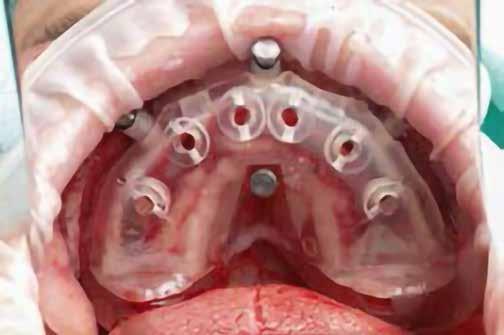

A-PRF membránokkal borítottuk (7. ábra). A mukogingivális lebenyt – annak megnyújtása nélkül – a helyére fektettük és varratokkal rögzítettük, per primam sebzárást nem végeztünk (8., 9. ábra). A varratokat 2 hét után távolítottuk el, a varratszedésig a sebgyógyulás támogatására per os 1000 mg/nap C- és 12 000 NE/nap D-vitamint adtunk (20). A műtéti beavatkozást 24 hét gyógyulási időszak követte, melynek során sem helyi, sem gyógyszeres kezelés nem történt, az esztétikum javítása érdekében a páciens ideiglenes kivehető fogpótlást használt. A csontos gyógyulás ellenőrzése és az implantáció tervezése céljából állcsonti CT felvételt készítettünk, illetve lenyomatvételt végeztünk. A CT felvételen tökéletes csontos gyógyulást észleltünk, az alveolaris csont volumene teljes mértékben megtartott volt (10. ábra), a klinikai kép is ennek megfelelően alakult (11., 12. ábra)

A Trishape Implant Studio™ a korábbi csont augmentáció területén, a felső állcsontnál áltagosnak számító D2-D3 csontminőséget jelzett (13. ábra). A lenyomat alapján készített gipszmodellt szkennelve virtuális mintát nyertünk. A CBCT felvétel és a virtuális modell adatait a Dual Scan protokoll (21) elveinek megfelelően használtuk fel az implantációs sablon (New Age Dental Kft, Nemeskéry Károly) készítéséhez (14., 15., 16. ábra). Az implantátum (Ankylos C/X A11) behelyezése teljesen navigált módon, 35 Ncm primer stabilitással történt (17., 18. ábra). Az implantátumra a fogtechnikus (D1 Dental Kft., Garamvári Csaba) által előzetesen